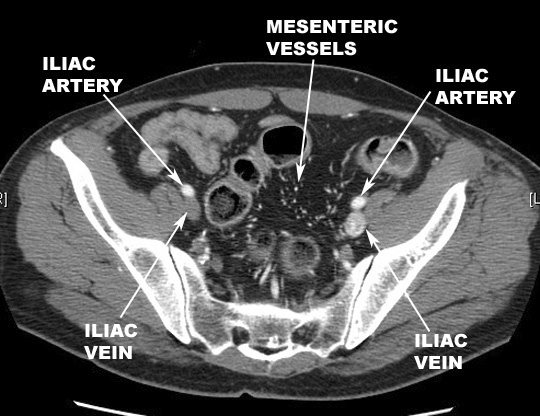

- Travels

inferolaterally for approximately five cm and terminates

as the internal

and external iliac arteries at the level of the pelvic inlet (L5-S1).

- Relationship

- Supplies

- Pelvis

- Lower extremities

- Genitals